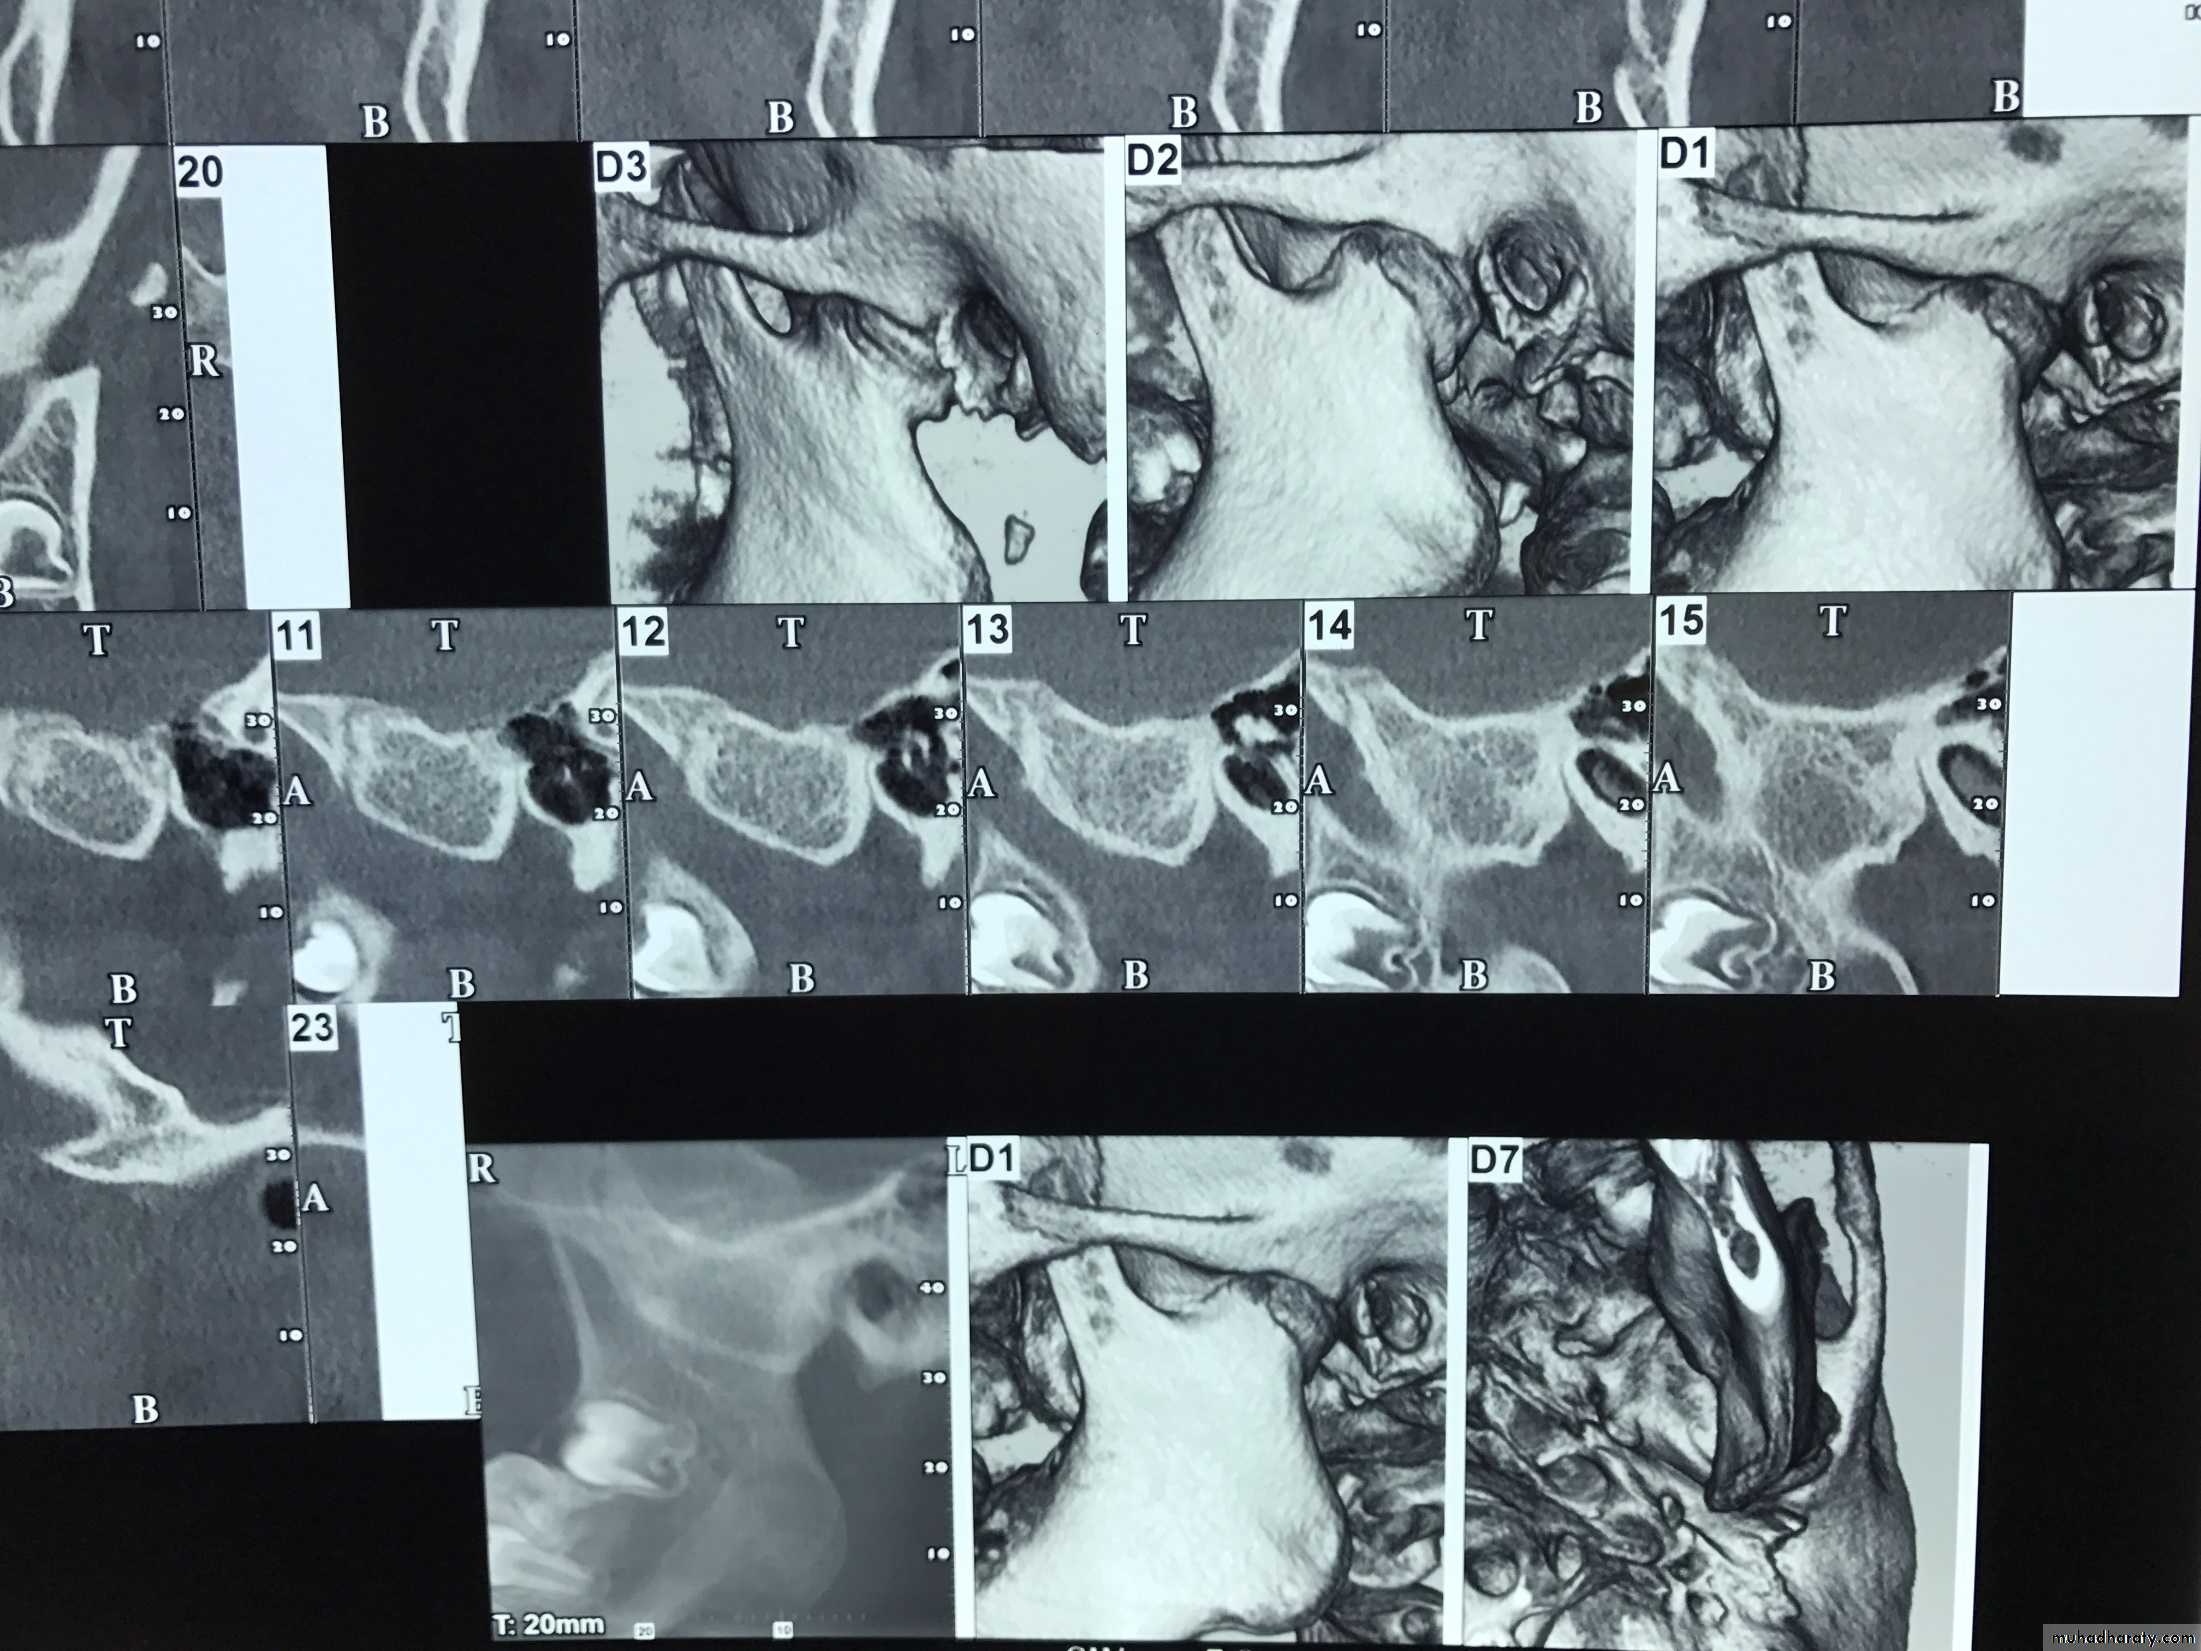

• Tomograms:

• this technique allows radiographical sectioning of the joint at deferent levels of the condyle and fossa complex which provides individual views visualizing the joint in slices from the medial to the lateral pole. these views eliminate bony super impostion, and overlap and provides a relatively clear picture of the bony anatomy of the joint.